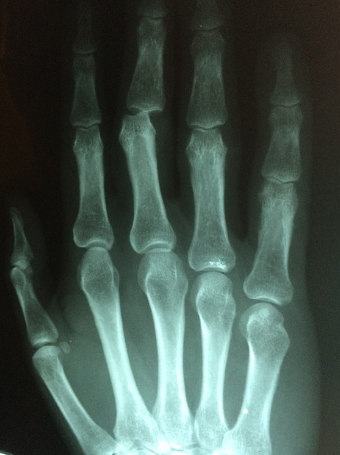

1) 손가락 퇴행성 관절염

이는 손가락 관절을 많이 사용해

뼈를 싸고 있던 연골이 닳아서 생기는 퇴행성 질환입니다.

흔히 관절염이라고 하면 무릎 등 큰 관절만 생각하는 경우가 많습니다

그러나 우리의 몸은 무수히 많은 뼈와

관절로 이루어져있고,

이 모든곳에 관절염이 생길 수 있습니다

대표적인 증상으로는 손가락 관절을

구성하는 뼈가 굵어지고

손이 변형되는 것 입니다